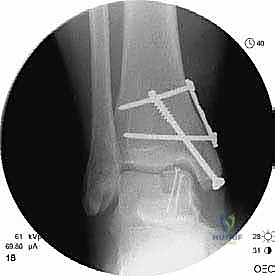

- التصوير بالأشعة السينية (X-rays): الخطوة الأولى لاستبعاد الكسور الكبيرة وتقييم المحاذاة العامة للعظام. قد تظهر الأشعة السينية الآفات الكبيرة، لكنها غالباً ما تفشل في إظهار التلف الغضروفي المبكر.

- التصوير المقطعي المحوسب (CT Scan): ضروري جداً للآفات الكبيرة. يوفر الـ CT صورة ثلاثية الأبعاد للعظم، مما يساعد الجراح في التخطيط الدقيق لعملية قطع العظم وحجم الطعم المطلوب زراعته.

ثالثاً: الحل الجذري - إعادة بناء الطعم الخيفي الهيكلي

بالنسبة للمرضى الذين يعانون من آلام مزمنة، وتظهر صورهم آفة كبيرة الحجم، عميقة، تحتوي على تكيسات ضخمة، أو تشمل حواف التالوس (الكتف)، تصبح إعادة بناء الطعم الخيفي الهيكلي هي الحل الأمثل والذهبي.

الغوص العميق في جراحة الطعم الخيفي الهيكلي (Structural Allograft Reconstruction)

يهدف هذا الإجراء العبقري إلى استبدال الغضروف والعظم التالفين والميتين بنسيج سليم تماماً مأخوذ من متبرع متوفى (طعم خيفي - Allograft). هذا الطعم يتم تعقيمه وحفظه في بنوك الأنسجة العالمية وفقاً لأعلى المعايير الطبية الصارمة لضمان خلوه من أي أمراض معدية والحفاظ على حيوية الخلايا الغضروفية.